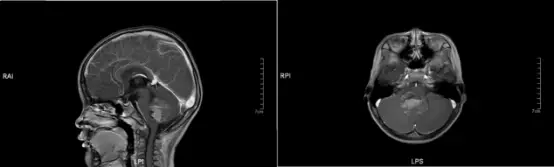

治疗经过 2017年10月26日,对患儿进行术前MRI(图1)。

图1 术前磁共振(MRI)图